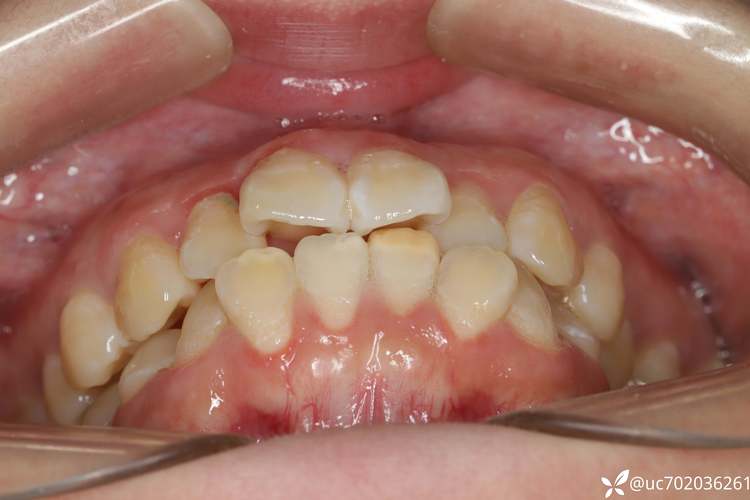

正畸治疗中,拔除第六颗牙(通常指上下颌第一前磨牙,即从门牙开始数的第六颗牙)以实现前牙内收,是解决牙列拥挤、前突等问题的经典手段,这种拔牙模式并非随意选择,而是基于严格的适应症评估和精细的生物力学设计,通过合理的支抗控制,在解除拥挤的同时改善面型与咬合功能,第一前磨牙位于尖牙与第一磨牙之间,牙根多为单根或双根(上颌多为双根,下颌多为单根),牙冠体积适中,拔除后对咀嚼功能的影响相对较小,且其位置靠近前牙,为前牙内收提供了充足的空间,因此成为正畸拔牙的常见选择并非偶然,并非所有正畸患者都需要拔六号牙,其适应症主要包括:牙列中度至重度拥挤,通过单纯磨牙前移无法解决;安氏Ⅱ类错颌,上前牙前突(深覆盖),需要大量前牙内收改善面型;上下牙弓前段存在间隙,但后段牙量充足,可通过拔除前磨牙关闭间隙;患者面部软组织较突,期望改善侧貌凸度,正畸医生会通过X线片(头影测量)、模型分析、口内检查等综合判断是否需要拔牙,拔六号牙收前牙的核心原理是“支抗控制”,拔除第一前磨牙后,两侧的牙齿会向中间移动,此时需要设计支抗,即控制后牙不前移或少量前移,让前牙向后移动(内收)占据拔牙间隙,支抗可分为弱支抗、中等支抗和强支抗,例如使用种植支抗(微种植钉)可以提供绝对支抗,确保后牙稳定,前牙高效内收,移动过程中,通过弓丝的弹性(如镍钛圆丝排齐,不锈钢方丝加力)施加持续、轻柔的力量,引导牙齿在牙槽骨内改建——压力侧牙槽骨吸收,张力侧牙槽骨增生,从而实现牙齿的平稳移动,治疗阶段需精细把控:术前评估阶段,医生需拍摄全景片、头颅侧位片,取研究模型,分析牙齿拥挤度、骨量、面部突度等指标;拔牙后初期(1-2周),等待伤口愈合,此时使用较细的镍钛圆丝排齐牙齿,避免加力过猛;间隙关闭期是关键阶段,通常采用滑动法(将弓丝放入托槽槽沟,通过橡皮链或弹簧牵引关闭间隙)或关闭曲法(在弓丝上弯制关闭曲,加力后牙齿移动),此阶段需每月复诊调整,控制移动速度(每月1-1.5mm);精细调整期(约3-6个月),调整咬合关系,如尖窝相对、边缘嵛对齐;保持期拆除矫治器后,需佩戴保持器(通常为透明压膜保持器或 Hawley 保持器)至少2年,夜间长期佩戴,防止复发,拔六号牙收前牙的优势显著:可解除中度至重度拥挤,排齐不齐的牙齿;前牙内收能有效改善凸嘴、瘪嘴等面型问题,使侧貌更协调;通过调整牙齿位置,可建立稳定的咬合关系,提高咀嚼效率;长期稳定性较高,若保持得当,复发风险较低,但需注意潜在风险:少数患者可能出现牙根吸收(移动过程中牙根尖端轻微吸收,通常不影响功能,但严重时需终止治疗);牙龈退缩(牙根暴露,多与口腔卫生不佳或牙齿移动速度过快有关);牙髓活力变化(少数患者可能出现暂时性敏感,一般可自行恢复);复发(若保持不当,前牙可能轻微前突,需终身佩戴保持器),治疗过程中,患者需严格配合:保持口腔卫生,每天刷牙3次,使用牙线、冲牙器,避免托槽周围食物残渣堆积;避免啃硬物(如坚果、骨头),防止托槽脱落;定期复诊(通常4-6周一次),以便医生调整加力;注意饮食调整,拔牙后1周内吃温凉软食,避免辛辣刺激,以下是拔六号牙收前牙的治疗阶段及注意事项简表: